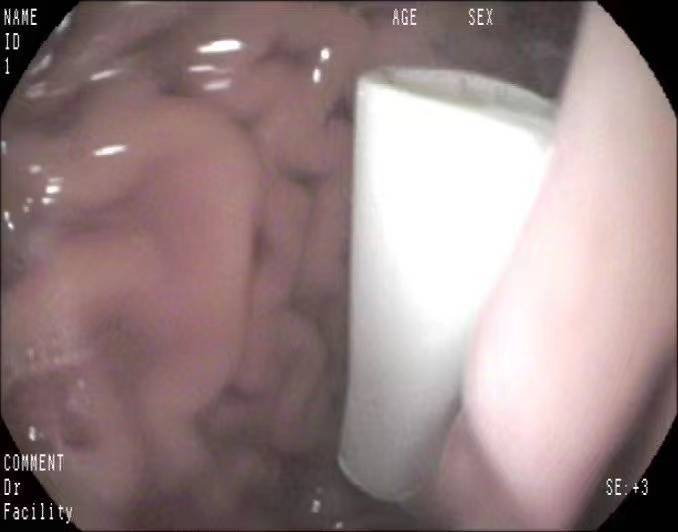

取笔画面。 消化内镜的医生和护士接到电话通知后,在帅帅完善术前检查前就全部赶到内镜中心,要趁笔盖掉到十二指肠之前把它取出来,避免外科开腹手术,减轻痛苦,让孩子早日恢复健康回到学校,不耽误他的学习。 在大家齐心协力合作下,从手术开始到结束仅仅用了三十分钟就将笔盖顺利取出。帅帅一醒来,第一句话就把大伙儿给逗乐了:“咦?!手术结束了吗?取出来了?才刚睡着就结束了,我还想再睡一会儿呢!”

取出的笔盖。